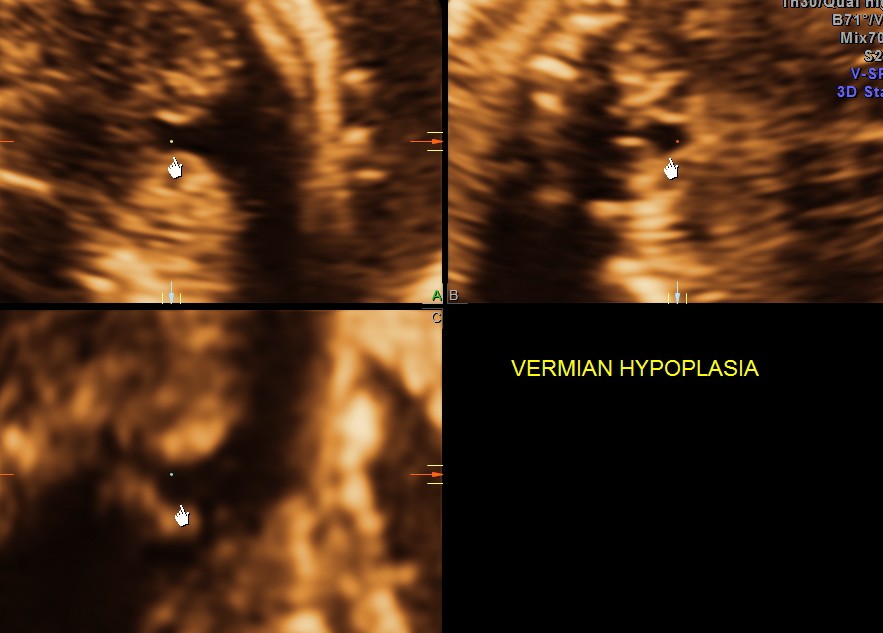

Ultrasound pictures of the fetal cranium are given below and showed cerebellar vermian dysgenesis .The buttocks sign can be appreciated.